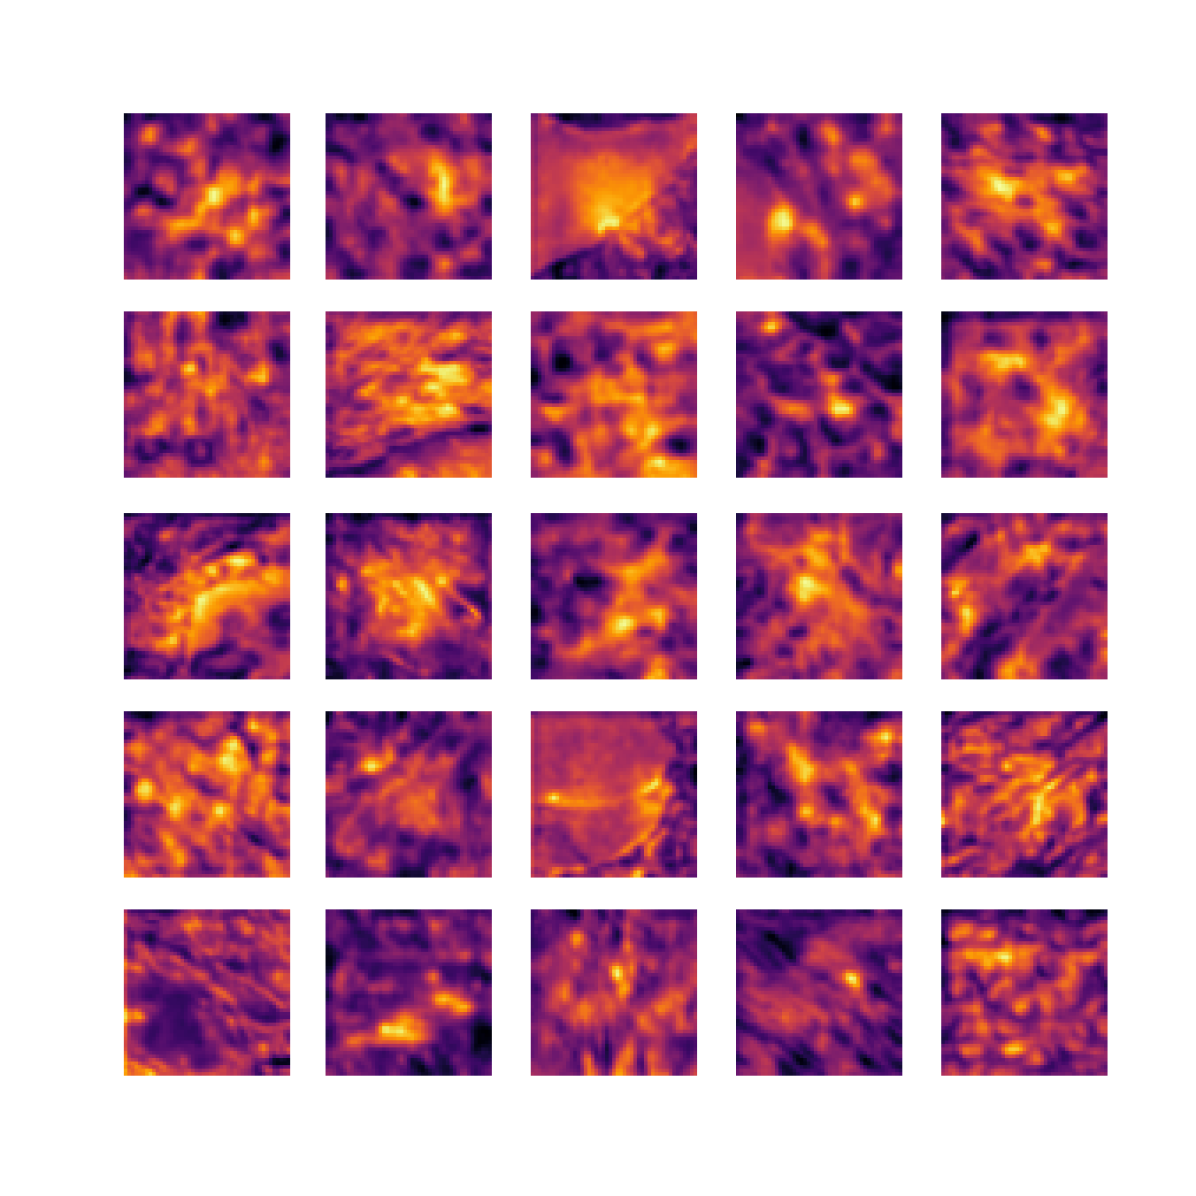

We also analyse the activation maps for each model using GradCAM as described in section S3. This offers more insight into the areas of the image which are contributing most heavily to the models’ representations. In Figure 4(b) we present some representative examples, however, a larger selection which was chosen at random is presented in Figures S10 to S25. The larger selection makes it easier to see the emergent patterns, including that privileged Siamese models tend to mainly identify features which are strongly present in both inputs, while unprivileged Siamese models tend to learn more diffuse features that are not specific to one cell phenotype or image region. TriDeNT ♆ incorporates both sets of features, learning both features specific to the privileged data and more the general features associated with unprivileged Siamese networks.

We can see in Figure 4(b) panel A that for ERG, the privileged Siamese model focuses almost exclusively on any nuclei which could be endothelial cells. As there are very few endothelial cells in the dataset, it could be an effective strategy to identify anything that could potentially be an endothelial cell to minimise the difference between the representations of the H&E model and the IF mask model. In the corresponding unprivileged Siamese image, we see that the model identifies some of these nuclei, albeit less strongly, but also focuses heavily on the other tissue and even the background, while strongly fixating on two spots of debris in the center of the image. This model has less ‘incentive’ to learn the weak features related to endothelial cells as these occur rarely and are not easy to detect, while more generic strong features such as the presence of connective tissue and the prevalence of background are more common and predictable from augmented images. We see that TriDeNT ♆ combines these two feature sets, strongly identifying nuclei while also identifying the connective tissue.

In panel C we see a similar pattern, with the privileged Siamese model fixating solely on the nuclei, while the TriDeNT ♆ model takes a more balanced approach. The unprivileged Siamese model appears to focus on a single cluster of nuclei while neglecting others, and similarly identifies an area of fibroblasts with its distinctive pattern but does not others.

In contrast to panels A and C which represent models with poor privileged Siamese results, panels B and D represent models whose privileged Siamese results were comparable to both TriDeNT ♆ and even the supervised baseline. It is therefore interesting to note that there are far more similarities between the privileged Siamese and TriDeNT ♆ models in both cases. Particularly in panel B, TriDeNT ♆ and the privileged Siamese model return virtually identical heatmaps, with both strongly identifying epithelial nuclei and neglecting the same areas of connective tissue. The unprivileged model in this case appears to focus solely on the centre of the image, giving a significantly different heatmap to the other panels.

Panel D again shows the previous pattern, with the privileged Siamese model identifying the features strongly present in the privileged data – fibroblasts – while neglecting the nuclei present. TriDeNT ♆ also strongly identifies the connective tissue, but, unlike the privileged Siamese model, does not completely neglect the nuclei. The unprivileged Siamese model primarily identifies background, and does not appear to identify the nuclei in this example.